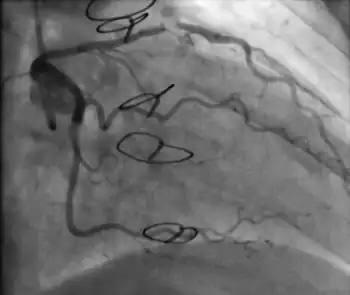

Primary angioplasty procedure in a person who had CAV after heart transplantation.[11]

Clinically significant CAV may require percutaneous coronary interventions for focal disease, but the likelihood of restenosis is high.[2] A repeat heart transplantation may be considered.[2]